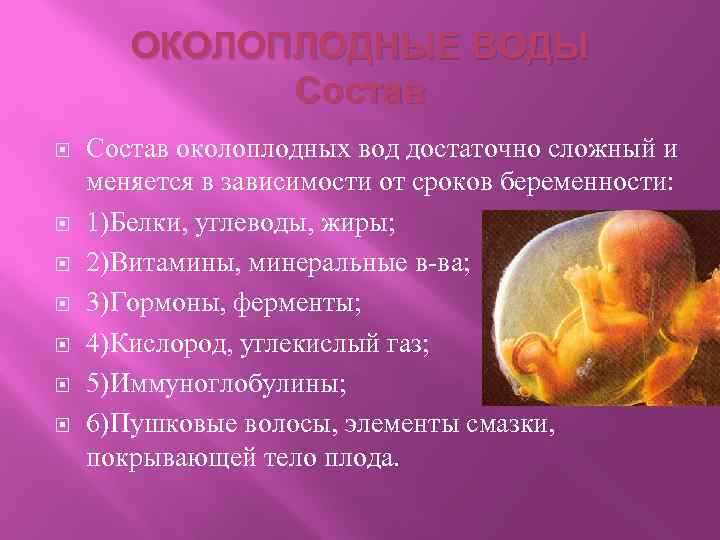

Амнион и Околоплодные Воды: Функции и Роль в Беременности